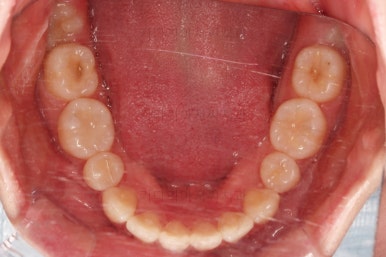

마찬가지로 초진 시 입안의 모습인데요.

전반적으로 약간 삐뚤지만 특히 윗니 앞니가 삐뚤고요.

송곳니는 덧니처럼 튀어나와 보이네요.

그리고 전반적으로 치아가 앞쪽으로 경사되어 있어서 앞니는 뻗친 느낌이 있네요.

가지런하게 하면서 앞니를 뒤로 당겨줘야 여러 가지 문제점들이 개선되기 때문에 발치교정을 했어요.